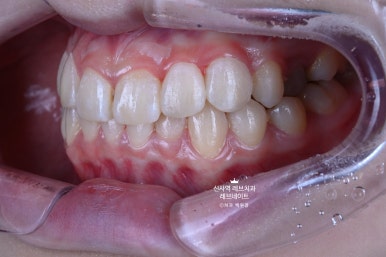

그냥 얼핏 보기엔 뭐.. 치열이 조금 틀어져 있네? 이 정도라고 생각이 드실텐데요

(저 또한 그랬습니다.)

이게 왠걸 ! 고개를 돌려보니 치아가 하나 없는겁니다...

어딨지? 하고 보니,

오른쪽 송곳니가 보다 안쪽에 있는 부정교합이라, 마치 치아하나가 없는 것 처럼 보이는 상태셨어요.

정면만 딱 보면 안보이는 것 같은데, 얘기하거나 웃을 때 엄청 잘 보이는 앞니 사이 공간이 있는거에요..

그리고 잘 보면, 치아들이 조금 뻐드러져 있기도 하고.. 뭔가 돌아가 있기도 하고..